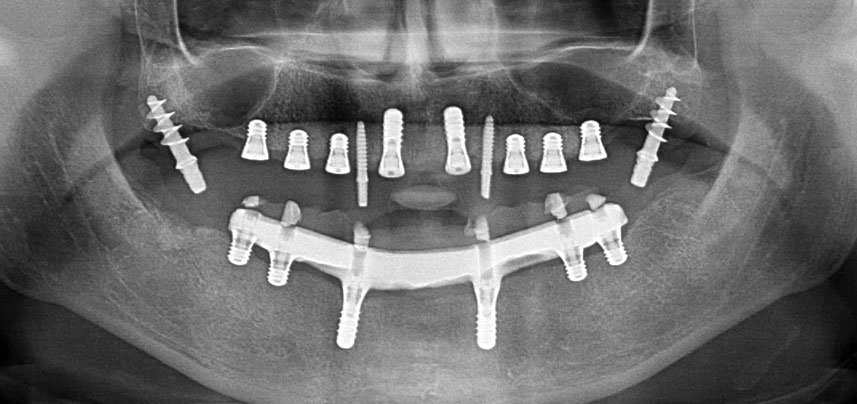

Drei Jahre später war es Zeit für eine gleichartige Oberkieferprothese. Basierend auf der DVT-Planung wurde durch Verwendung kurzer Implantate eine Sinusaugmentation vermieden und die geplanten Implantatpositionen wurden mit einer Bohrschablone auf den Kieferkamm übertragen (Abb. 1 und 2).

Wegen des relativ harten Knochens (D2) an den Positionen 11 und 21 wurden die 10 mm langen Implantatlager in diesem Bereich abschließend mit einem 4-mm-Spiralbohrer, dem chirurgischen Winkelstück WS-75 L von W&H und dem W&H Implantmed Implantologiemotor in Verbindung mit dem optionalen W&H Osstell ISQ module präpariert. Im Gegensatz dazu wurde der weiche Knochen der Implantatlager im Seitenzahnbereich mit dem Piezomed I3P auf den abschließenden Durchmesser von 3 mm erweitert. Die Implantate wurden dann transgingival eingesetzt, die Einheildauer betrug drei Monate (Abb. 6-10). Die vorhandene Prothese wurde auf vier provisorischen Implantaten abgestützt (Abb. 8).